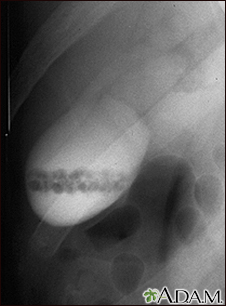

Gallstones, cholangiogramBackGallstones, cholangiogramA cholecystogram in a patient with gallstones. E-mail FormEmail ResultsName:Email address:Recipients Name:Recipients address:Message: